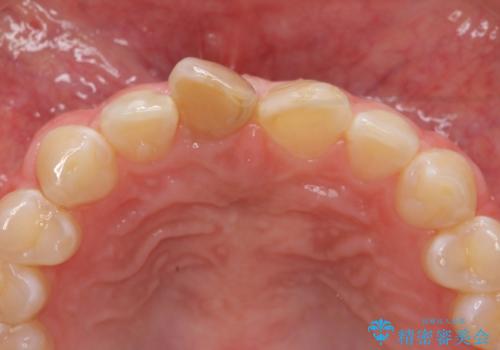

前歯をきれいにしたい ジルコニアクラウンによる審美治療

- 前歯の見た目の改善を求めて来院されました。

ジルコニアクラウンによる審美性の改善を計画します。

失活歯のため捻転を改善し、根管治療は特に希望されなかったのでそのままとしました。

今回失活歯であったため捻転を取り反対側の前歯に揃えて補綴を行うことができました。